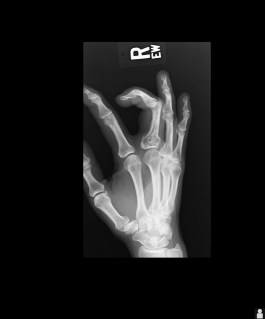

The reason…on June 1st I was hiking with some friends, fell crossing a stream and broke my finger. It sounds harmless enough but it is my middle finger on my right hand. Of course I am right-handed. So with a splint that basically immobilizes my entire right hand, using the computer, writing, or doing anything has been a challenge.

The x-rays taken at the time also revealed an enchondroma (benign bone tumor) in the knuckle.

That means surgery in July, so more recovery time. Sigh!